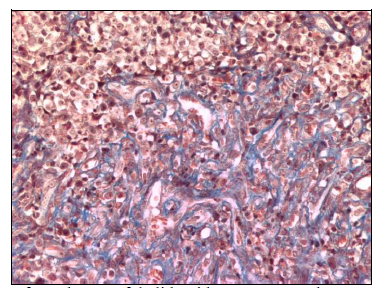

At day 14 of treatment, with thalidomide, the changes were more noticeable especially the vacuolization of the cytoplasm, nuclear degenerative changes were more intense including intense swelling and picnosis. The typical histological arquitecture of this tumor was distorted by a more intense lymphocyte infiltration and fibrous tissue proliferation that dominated in some areas (Figure 5).

Figure 5 CTVT tissue section from day 14 of thalidomide treatment. A large area o fibrosis is observed with some infiltrative lymphocytes and vacuolar degenerative changes in remaining tumoral cells Masson Stain (200X).